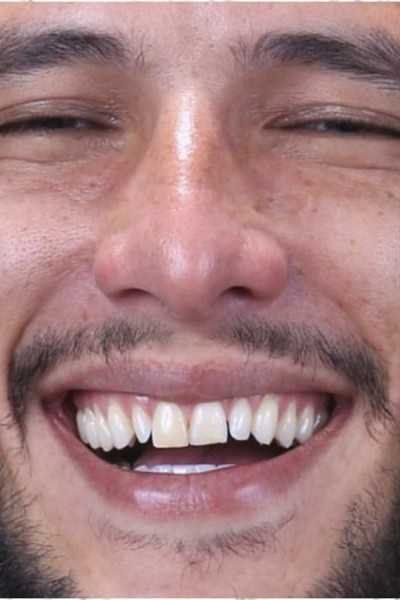

Озеров Петр специализируется на хирургической стоматологии и импланталогии, блестящий специалист по лечению и удалению кисты. Является постоянным участником курсов, семинаров и международных конгрессов по имплантологии и ортопедии. Петр Владимирович проводит протезирование как классическими методиками керамикой и металлокерамикой, так и протезами на драгсплавах (диоксид циркония, алюминий), и эстетическое протезирование винирами и люминирами. Кроме протезирования и имплантации, доктор выполняет и хирургическую подготовку к ним: операции по костной пластике с применением искусственной кости и аутокости (собственной кости пациента).